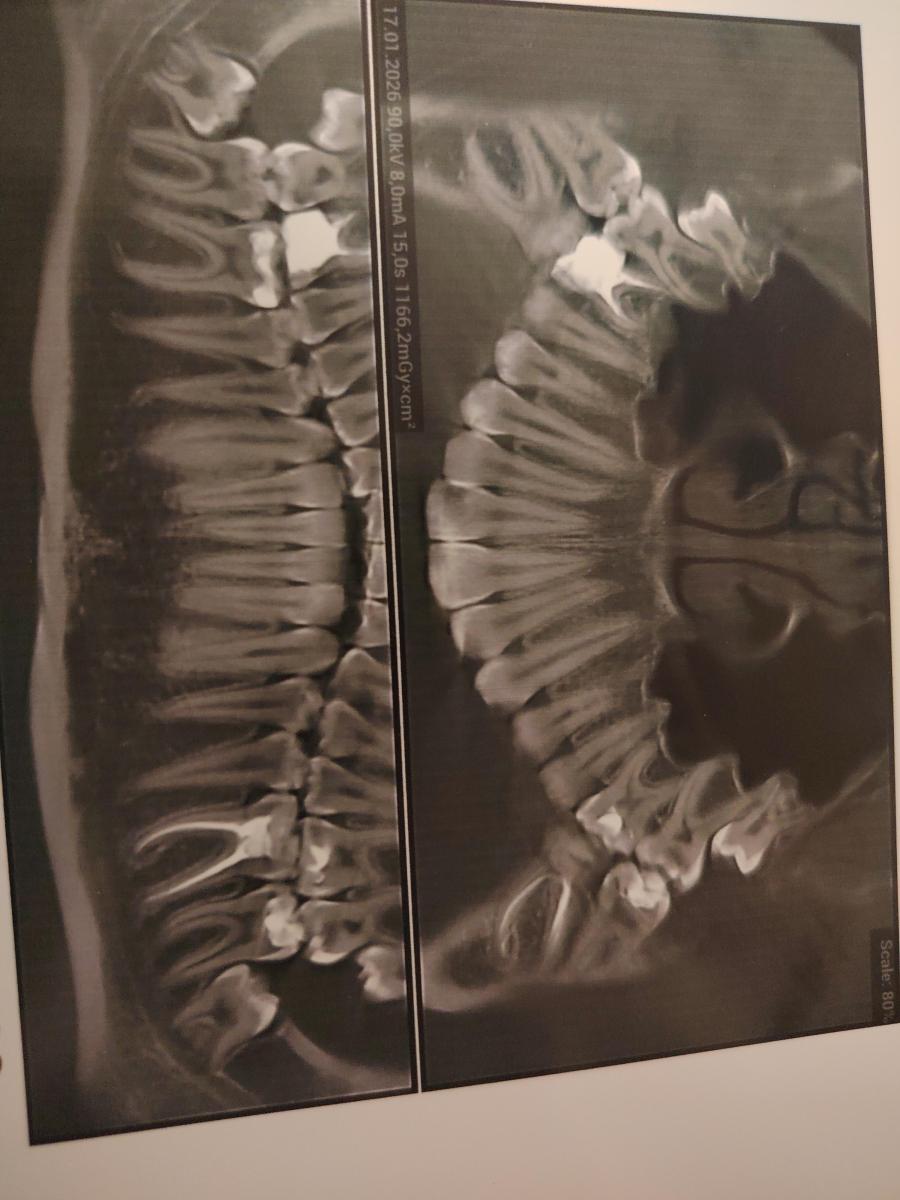

На снимке есть кариес в 26-27, однозначно. Их лечили?

Анна Адеева, 27 лечила недавно, на счёт 27 не сказали ничего даже. Спасибо! А справа 16-17 нет кариеса??

Справа, в 17 есть медиальный кариес